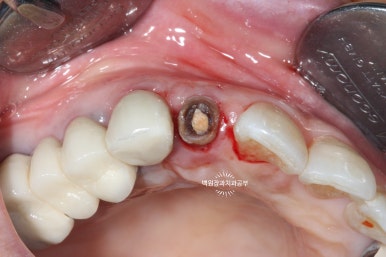

치료를 마친 후 체크업!!

치료를 모두 마친 뒤 보았을 때 치아의 동요도는 상당히 줄어들어 사용할 수 있을 정도로 흔들림이 적어졌습니다.

보시는 상태는 외과적 정출술 후 약 3개월이 지난 상태이고 신경치료와 보철치료는 모두 완료되었습니다.

임플란트가 아니라 치아를 이용하여 치료하였기 때문에, 잇몸의 질감과 모양이 살아있어 꽤나 심미적입니다.

(pink esthetic)